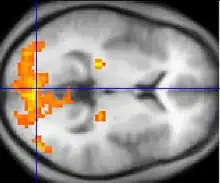

Teorien om spejlneuronssystemet antager, at ændringer i udviklingen af spejlneuroner forstyrrer imitation og fører til Aspergers kerneelement, som er social forringelse.[46][47] For eksempel viste en enkelt undersøgelse, at aktiveringen af kredsløbene relateret til imitation er forsinket i personer med Aspergers syndrom.[48] Denne teori svarer godt til andre teorier om sociale kognition som theory of mind, der antager, at autistisk adfærd skyldes en begrænset evnen til at tillægge sig selv og andre mentale tilstande.[49]